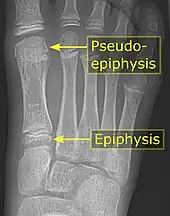

The first metatarsal bone is the bone in the foot just behind the big toe. The first metatarsal bone is the shortest of the metatarsal bones and by far the thickest and strongest of them.[1]

Like the four other metatarsals, it can be divided into three parts: base, body and head. The base is the part closest to the ankle and the head is closest to the big toe. The narrowed part in the middle is referred to as the body of the bone. The bone is somewhat flattened, giving it two sides: the plantar (towards the sole of the foot) and the dorsal side (the area facing upwards while standing).[1]